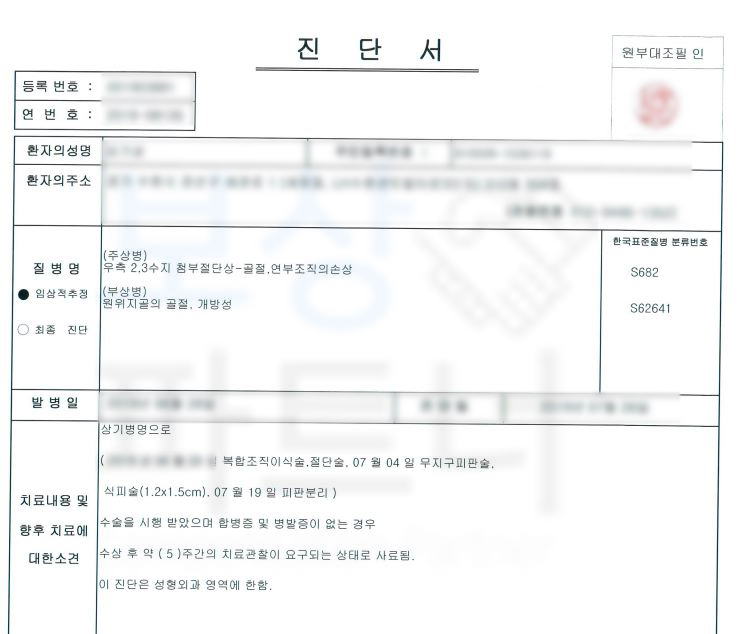

보상파트너에 연락주신 김@@님은 2수지 3수지 원위지골 골절 S62641 S682 진단받아 수술을 받게 되었습니다.

손가락에 철심 즉 핀고정은 안한신 상황이었습니다. 보상파트너는 먼저 김@@님의 보험증권을 받아 분석해드렸습니다.

가입시기별로 다른 보험약관을 분석한 결과, 재해자의 손가락압궤손상에 대해 보험금 청구 가능성을 확인 한 뒤 사건을 수임받아 진행하게 되었는데요,

해당사건은 굳이 장해진다서 발급 없이 영상CD와 함께 손해사정서 및 증빙자료를 송부하였습니다.